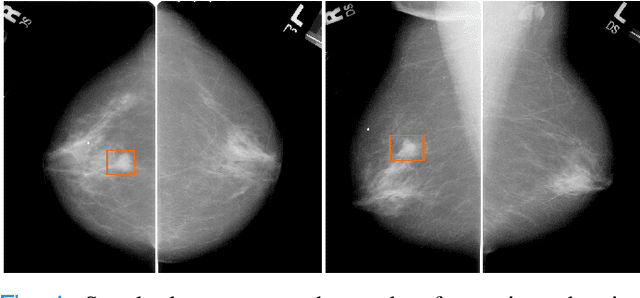

Abstract:Machine learning and deep learning methods have become essential for computer-assisted prediction in medicine, with a growing number of applications also in the field of mammography. Typically these algorithms are trained for a specific task, e.g., the classification of lesions or the prediction of a mammogram's pathology status. To obtain a comprehensive view of a patient, models which were all trained for the same task(s) are subsequently ensembled or combined. In this work, we propose a pipeline approach, where we first train a set of individual, task-specific models and subsequently investigate the fusion thereof, which is in contrast to the standard model ensembling strategy. We fuse model predictions and high-level features from deep learning models with hybrid patient models to build stronger predictors on patient level. To this end, we propose a multi-branch deep learning model which efficiently fuses features across different tasks and mammograms to obtain a comprehensive patient-level prediction. We train and evaluate our full pipeline on public mammography data, i.e., DDSM and its curated version CBIS-DDSM, and report an AUC score of 0.962 for predicting the presence of any lesion and 0.791 for predicting the presence of malignant lesions on patient level. Overall, our fusion approaches improve AUC scores significantly by up to 0.04 compared to standard model ensembling. Moreover, by providing not only global patient-level predictions but also task-specific model results that are related to radiological features, our pipeline aims to closely support the reading workflow of radiologists.

Abstract:The success of machine learning methods for computer vision tasks has driven a surge in computer assisted prediction for medicine and biology. Based on a data-driven relationship between input image and pathological classification, these predictors deliver unprecedented accuracy. Yet, the numerous approaches trying to explain the causality of this learned relationship have fallen short: time constraints, coarse, diffuse and at times misleading results, caused by the employment of heuristic techniques like Gaussian noise and blurring, have hindered their clinical adoption. In this work, we discuss and overcome these obstacles by introducing a neural-network based attribution method, applicable to any trained predictor. Our solution identifies salient regions of an input image in a single forward-pass by measuring the effect of local image-perturbations on a predictor's score. We replace heuristic techniques with a strong neighborhood conditioned inpainting approach, avoiding anatomically implausible, hence adversarial artifacts. We evaluate on public mammography data and compare against existing state-of-the-art methods. Furthermore, we exemplify the approach's generalizability by demonstrating results on chest X-rays. Our solution shows, both quantitatively and qualitatively, a significant reduction of localization ambiguity and clearer conveying results, without sacrificing time efficiency.

Abstract:Clinical applicability of automated decision support systems depends on a robust, well-understood classification interpretation. Artificial neural networks while achieving class-leading scores fall short in this regard. Therefore, numerous approaches have been proposed that map a salient region of an image to a diagnostic classification. Utilizing heuristic methodology, like blurring and noise, they tend to produce diffuse, sometimes misleading results, hindering their general adoption. In this work we overcome these issues by presenting a model agnostic saliency mapping framework tailored to medical imaging. We replace heuristic techniques with a strong neighborhood conditioned inpainting approach, which avoids anatomically implausible artefacts. We formulate saliency attribution as a map-quality optimization task, enforcing constrained and focused attributions. Experiments on public mammography data show quantitatively and qualitatively more precise localization and clearer conveying results than existing state-of-the-art methods.